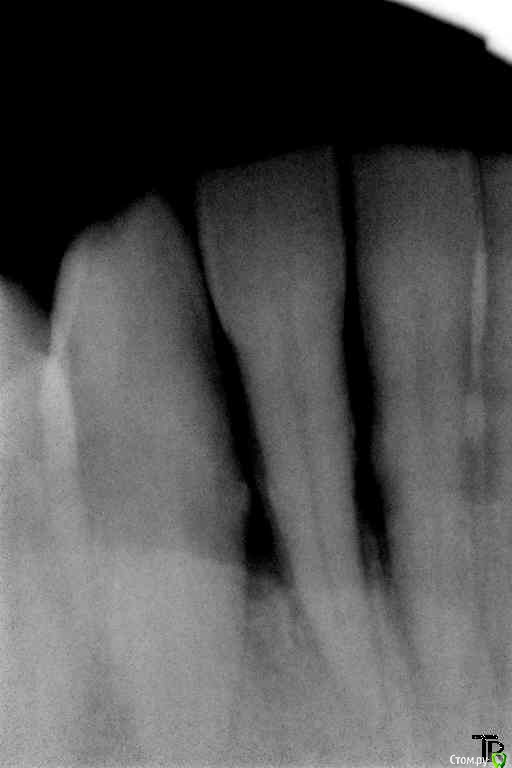

Витторио Орлионе Опубликовано 14 февраля, 2016 Поделиться Опубликовано 14 февраля, 2016 12.02.2016 Обратился Мужчина 72 года рождения с жалобами на боли и припухлость в области фронта нижней челюсти, на зубах налёт от стоматотофита, рецессия десны и резорбция кости,подижность 2 степени у зубов 4.2, 4.1 и 3 степени у зубов 3.1 и 3.2 десна вздулась в области зуба 3.2. Перкуссия да и просто прикосновения вызывали жуткие боли. Вколов 2 карпулы ультракаин дс форте инфильтративно + лидокаин, так и не обезболились, хотя губа занемела. Промыл хлоргексидином и оставил смесь из метрогила и трихопола под дессной, пациент при этом от боли вжимался в кресло. А как встал, ноющие боли прошли, а до зубов по прежнему не дотронуться. До посещения начал пить аугментин. Был 2й день приёма. Пришёл 14.02. Не болит, припухлость спала. 2 карпулы ультракаина дс форте не обезболилил. манипуляции повторил. Отправил до наступления реммиссии. Снимки прилагаются. Вопросы:Как обезбаливать в таких случаях?Удалять ли 3.2?Обязателен ли открытый кюретаж?Да и вообще как бы вы его вели? Ссылка на комментарий